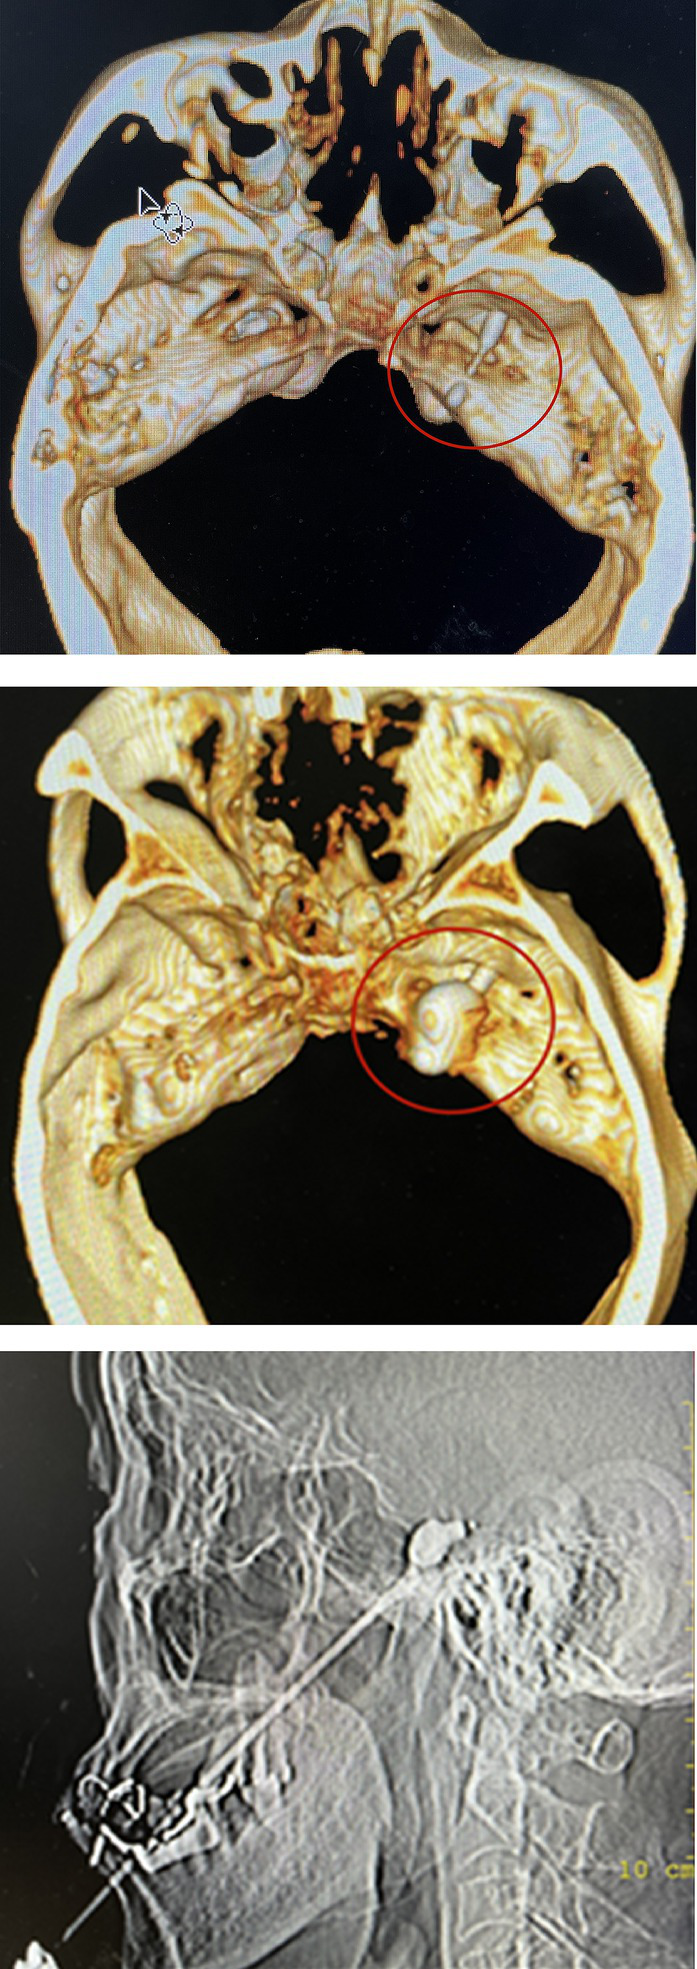

PBC

The patient remained awake during the operation and was placed in the supine position with the head tilted backward. ECG monitoring was routinely performed to monitor blood pressure, heart rate, and oxygen saturation. Furthermore, midazolam (0.03 mg/kg) was injected intravenously for sedation before surgery. A 22G local anesthesia needle, 10 cm in length, was used for a puncture, and 1% lidocaine (0.5 mL) was injected into the trigeminal nerve ganglia of the foramen ovale under CT guidance. Then a 14G balloon puncture needle was inserted along the original path. The needle tip entered the foramen ovale, and a No. 4 Fogarty balloon catheter was inserted. After confirming the correct location, 0.5–0.8 mL iodohexyl was injected into the catheter to inflate the balloon. The balloon and its position were adjusted during the lateral CT scan of the skull until a pear-shaped image was obtained, as shown in Figure 2. The catheter was removed after applying pressure for 3 min.

Figure 2

The location of balloon catheter can be determined by inserting balloon catheter under CT-guided. After the iohexol was injected, a “pear shaped image” was displayed on lateral CT imaging, indicating successful surgery.

In the PBC group, one patient still experienced postoperative pain, which may be related to the absence of a standard pear shape during the operation, as shown in Figure 4. PBC was administered again 10 days later, and the pain resolved.

Figure 4

The pear image does not appear. It indicates no pressure on trigeminal ganglion.

The key to PBC success is a pear-shaped image at the end of the catheter (22). The pear-shaped projection indicates that the balloon entered Meckel’s cavity. Nerve fibers that cause conduction pain can be effectively damaged. The oval shape indicates that the balloon did not enter the Meckel’s cavity, and the dumbbell type indicates that the balloon was too deep. Nevertheless, the latter two methods do not achieve satisfactory efficacy (23). In patients with recurrent pain, the anatomical structure may be damaged by previous treatment, which can cause difficulties in PRT and PBC. In the PBC group, one patient did not develop an ideal pear shape during the operation, and the pain was not controlled. After 10 days, PBC was performed. After repeated adjustments of the catheter position, a satisfactory figure was obtained, and the pain disappeared.